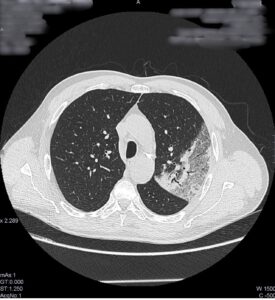

TC de tórax sin contraste intravenoso